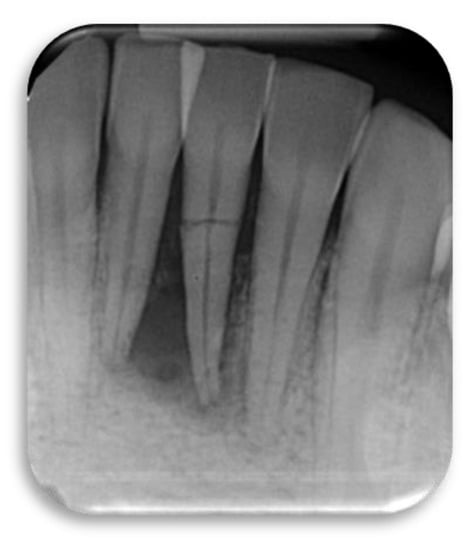

Figure 5.

Clinical scenario of a 17 years-old adolescent hit by a baseball ball in the anterior maxillary region. The boy presented to the Periodontal Department at Tufts University, Boston USA with crown fracture of left central incisor (#9) (a,b). Peri-apical radiograph show apical radiolucency, sign of necrosis. After the diagnosis, CaOH2 was applied. The root canal definitive treatment was completed but after 2 months the patient still presented with a fistula, that was tracked via a gutta-percha point. A CBCT scan was performed in order to diagnose the extent of the peri-apical lesion (c in sequence). The extent of the lesion did not suggest an endodontic therapy revision. Exploratory surgery was performed in order to rule out tooth fracture (d). The apex was resected in order to access the palatal aspect of the tooth. A PA radiograph was taken in order to verify correct apex resection and endodontic retrograde seal (e). Due to active patient skeletal growth, a decision was made to enucleate the endodontic cyst and treat the cavity with bone grafting material, in order to preserve the site for future implant placement (f,g). PA radiograph comparison before and after grafting placement (h,i). The patient was followed up for 2 months, and a fistula was identified apical to #9 (l). Tooth #10 was diagnosed as necrotic. A root canal was performed (m) and the apical radiolucency and fistula were resolved at 1 month follow up (n).